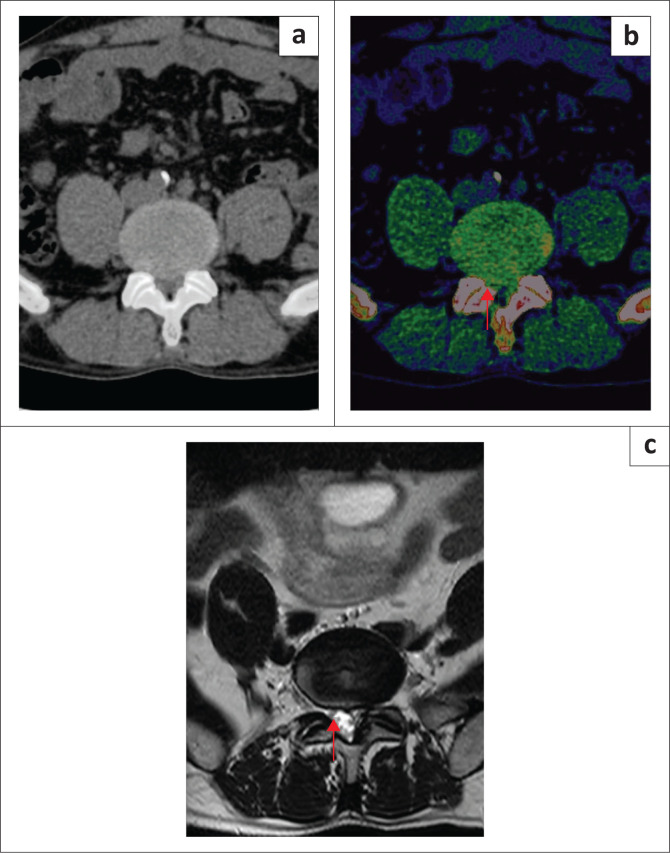

Method: The retrospective study included 84 patients between 01 July 2023 to 31 December 2023 who underwent DECT and 1.5-T MRI within 1 week. Four radiologists, blinded to the clinical and MRI information, independently evaluated the standard CT series and DECT series with ED reconstructions for lumbar disc herniation and spinal nerve root impingement. The gold standard for comparison was lumbar spine MRI, and diagnostic accuracy was measured with sensitivity and specificity.

Results: MRI revealed 417 lumbar disc herniations. Dual-energy computed tomography with ED reconstruction showed higher sensitivity (86.36% [532/616] vs. 57.79% [356/616]) and specificity (96.86% [1019/1052] vs. 95.82% [1008/1052]) for the detection of lumbar disc herniation compared to standard CT.

Conclusion: Dual-energy computed tomography with ED reconstruction shows better diagnostic performance for the detection of lumbar disc herniation compared to standard CT and can be a useful alternative imaging modality when MRI is contraindicated or unavailable.